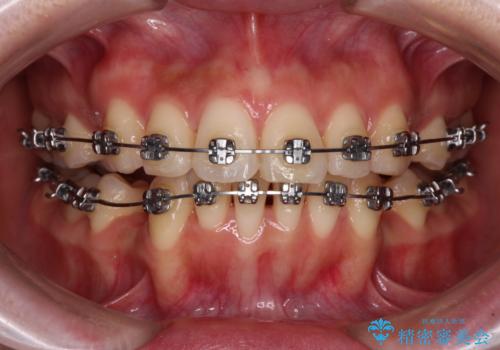

- メタルブラケット

- 治療期間

- 2年2ヶ月

上下ともに歯列が前方に突出していたため、上下左右の第一小臼歯4本を抜去し、ワイヤー装置による矯正治療を行うこととしました。